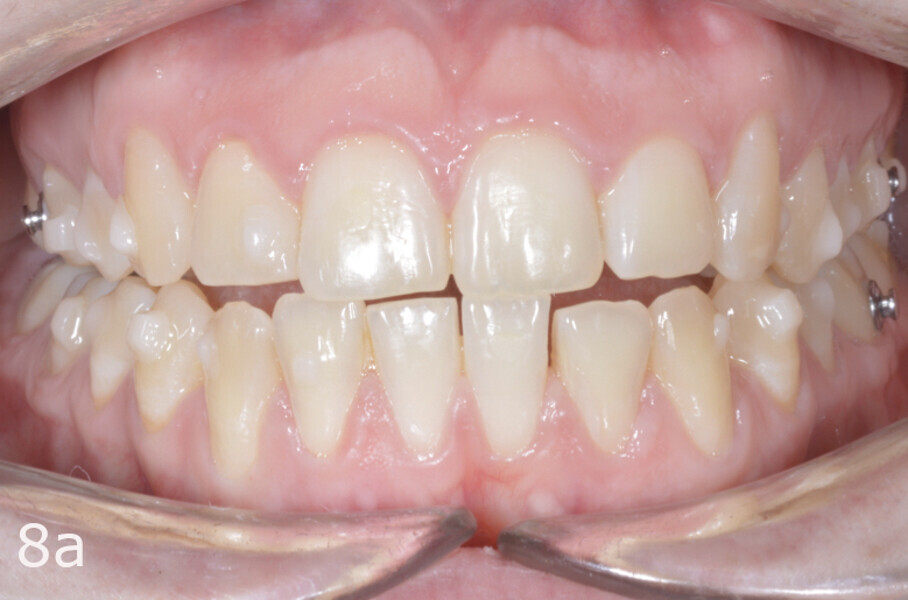

The 23-year-old dolichofacial female patient complained of not being able to chew properly. Facial examination showed a convex profile, an enlarged lower facial height, and a skeletal Class III malocclusion (Figs. 1–3). Intra-oral examination revealed an Angle Class III right subdivision malocclusion, anterior open bite, no overjet and a maxillary dental midline deviated about 3 mm to the right compared with the mandibular dental midline (Fig. 4). The panoramic radiograph confirmed previous extraction of the maxillary right first premolar and the presence of all four third molars (Figs. 5 & 6).

The treatment objectives included closing the anterior open bite, achieving a bilateral Angle Class I relationship and a proper overjet and overbite, correcting the midline discrepancies, and achieving a profile harmonisation. The treatment plan consisted of orthodontic camouflage treatment with asymmetric distalisation in three of the four quadrants using Invisalign aligners (Align Technology) and third molar extraction. The Invisalign Comprehensive package was chosen, and 63 pairs of aligners were used (Figs. 7–10). Each aligner was worn for 20 hours a day for one week each. The use of Class III elastics on both sides was indicated. Afterwards, ten refinement aligners were needed to improve the interdigitation on the right side (Figs. 11 & 12).